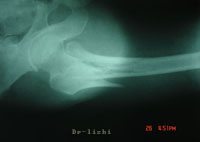

外傷後局部疼痛、腫脹、壓痛和功能障礙均較明顯,有時髖外側可見皮下瘀血斑,遠側骨折段處於極度外鏇位,嚴重者可達90°外鏇。病人多為老年人,傷後髖部疼痛,不能站立或行走。下肢短縮及外鏇畸形明顯,無移位的嵌插骨折或移位較少的穩定骨折,上述症狀比較輕微。檢查時可見患側粗隆升高,局部可見腫脹及瘀斑,局部壓痛明顯。扣擊足跟部常引起患處劇烈疼痛。往往需經X線檢查後,才能確定診斷,並根據X線片進行分型。

(3)、X線攝片可見骨折

股骨粗隆間骨折和股骨頸骨折的受傷姿勢,臨床表現大致相同,兩者容易混淆,應注意鑑別診斷,一般說來,粗隆間骨折因局部血運豐富、腫脹、瘀斑明顯,疼痛亦較劇烈,都比股骨頸骨折嚴重;前者的壓痛點多在大粗隆部,後者的壓痛點多在腹股向韌帶中點的外下方。X線片可幫助鑑別。

下肢短縮及外鏇畸形明顯,無移位的嵌插骨折或移位較少的穩定骨折,上述症狀比較輕微。檢查時可見患側粗隆升高,局部可見腫脹及瘀斑,局部壓痛明顯。扣擊足跟部常引起患處劇烈疼痛。往往需經X線檢查後,才能確定診斷,並根據X線片進行分型。

診斷明顯外傷史,患肢疼痛,活動受限。Х線片可確定骨折部位及移位情況。併發症肺炎;褥瘡;泌尿系感染患者多為高齡老人,首先注意全身情況,預防由於骨折後臥床不起而引起危及生命的各種併發症,如肺炎、褥瘡和泌尿系感染等。骨折治療目的是防止發生髖內翻畸形,具體治療方法應根據骨折類型、移位情況、患者年齡和全身情況,分別採取不同方法。